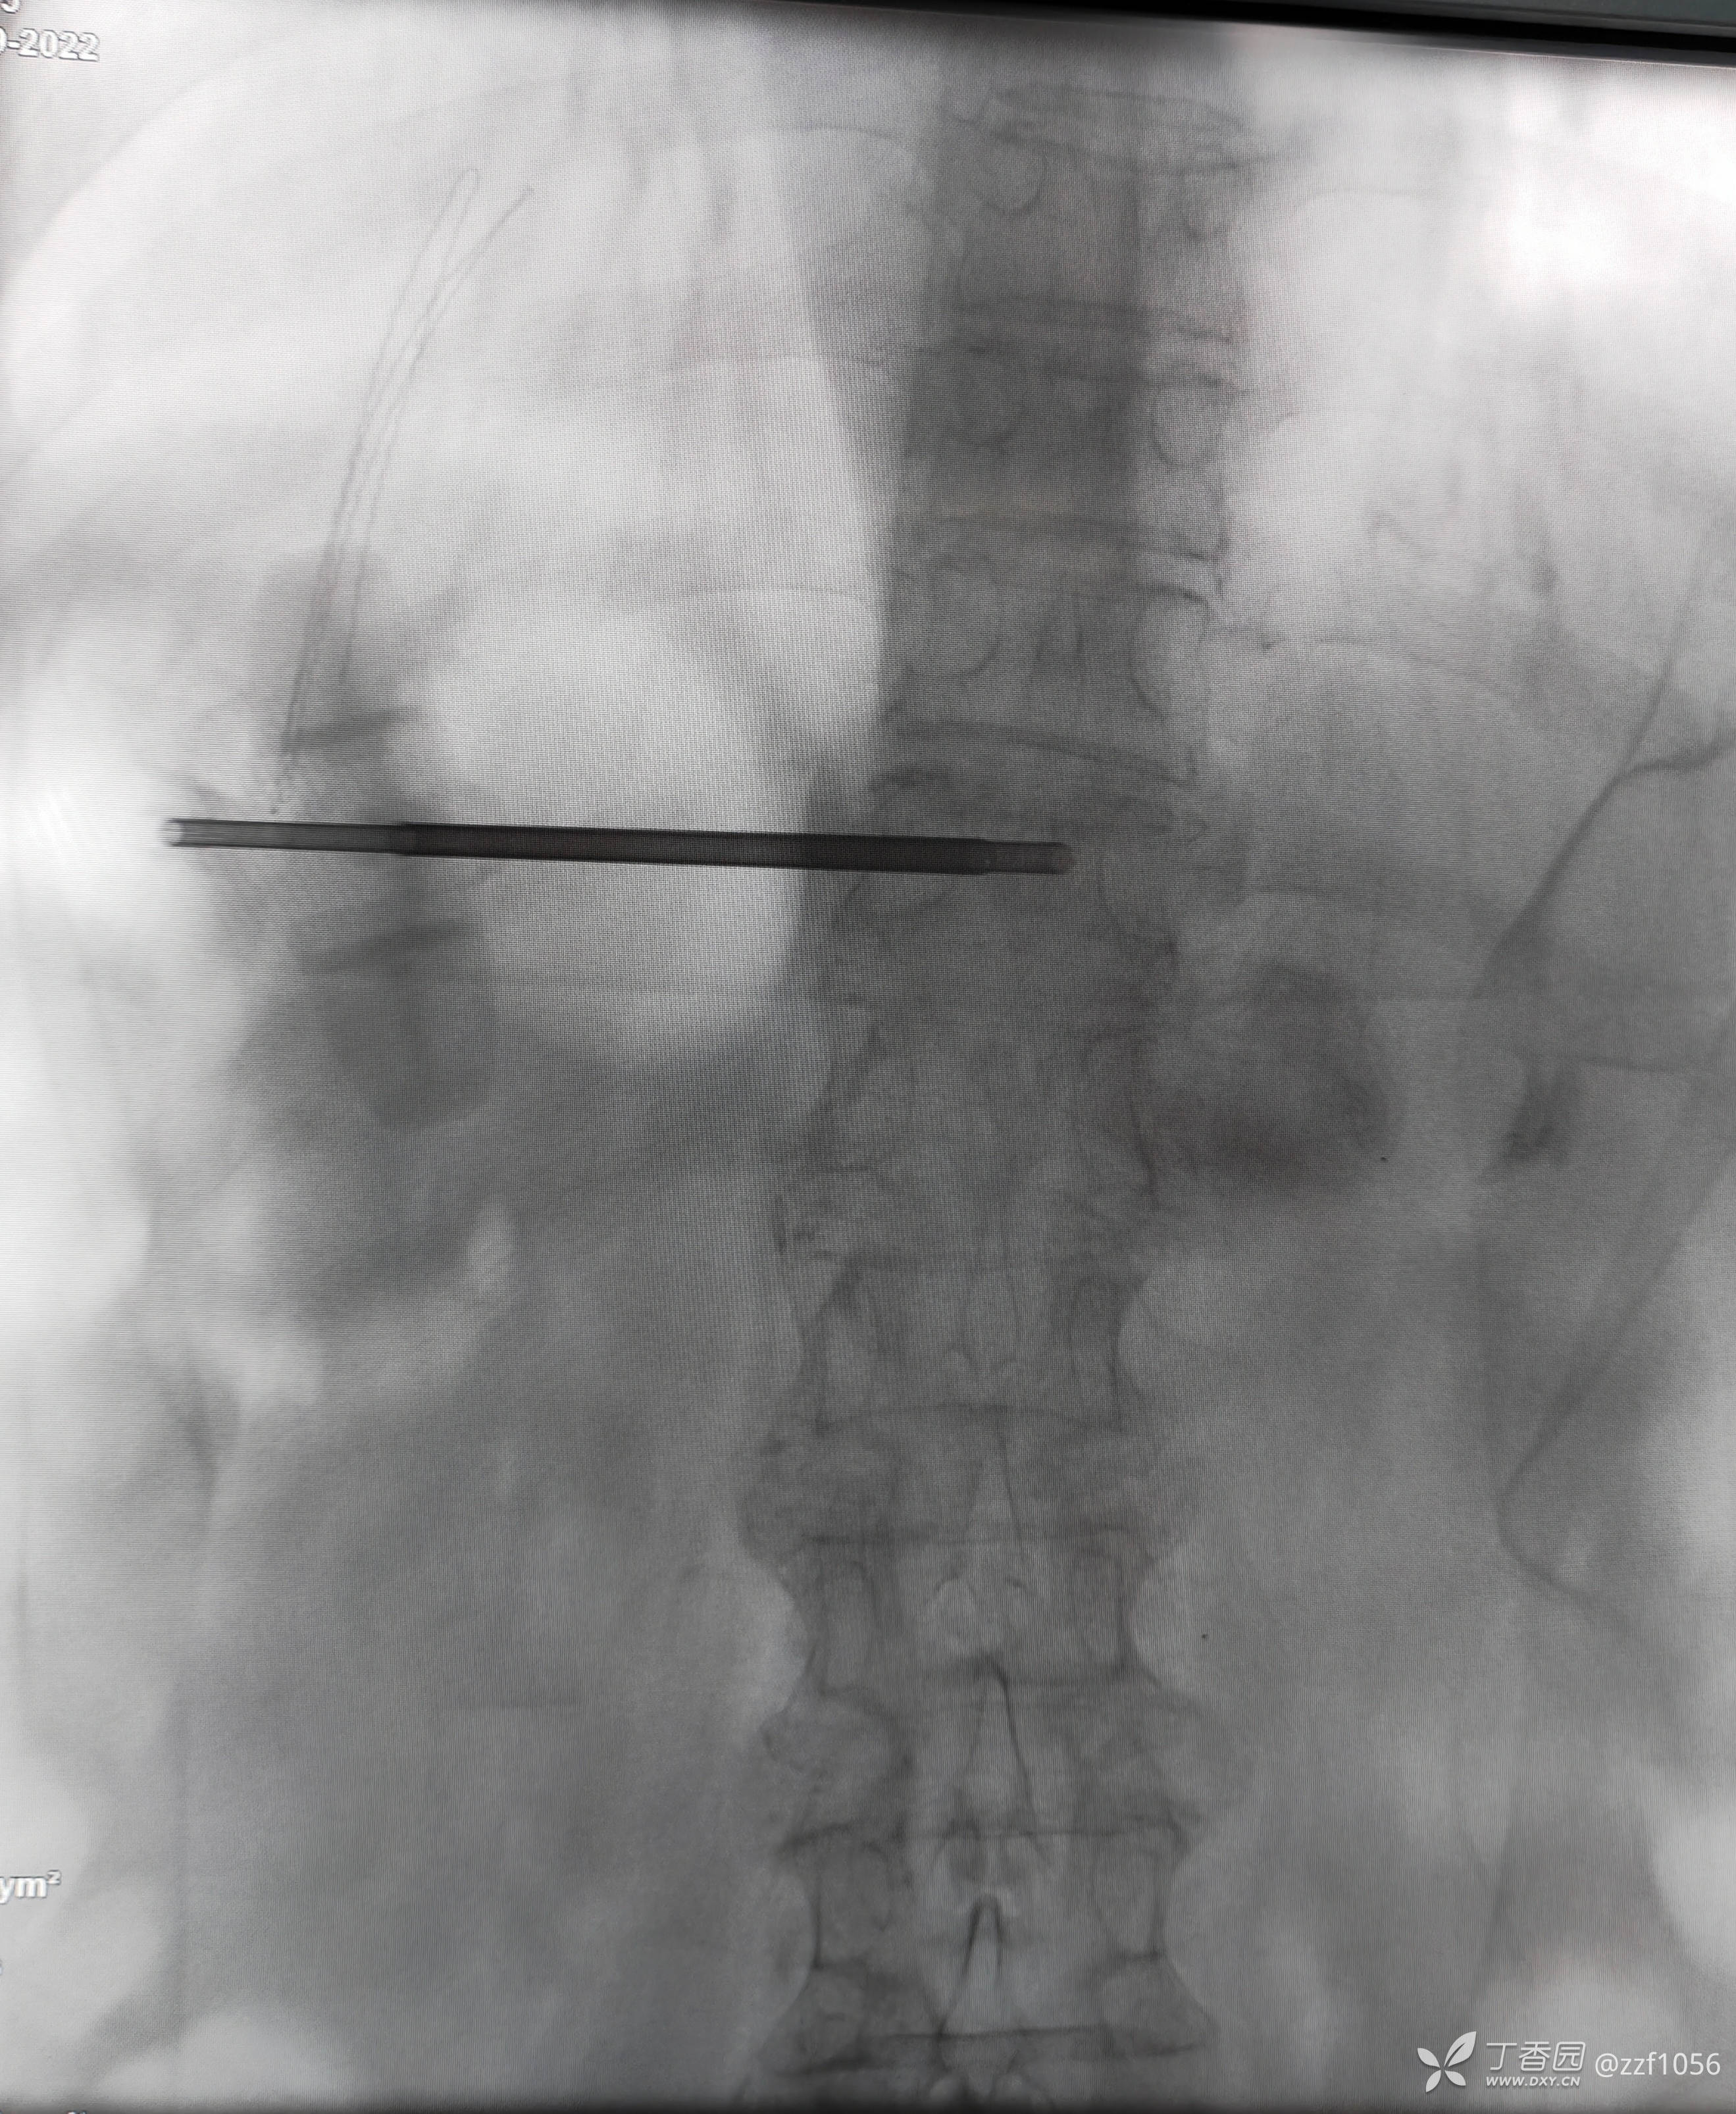

病例二(非我病例,单侧穿刺)

患者老年男性,85岁

第一次甲医院术后

战友们觉得如何?骨髓泥量约3、4ml,那么单侧穿刺能否说的过去?